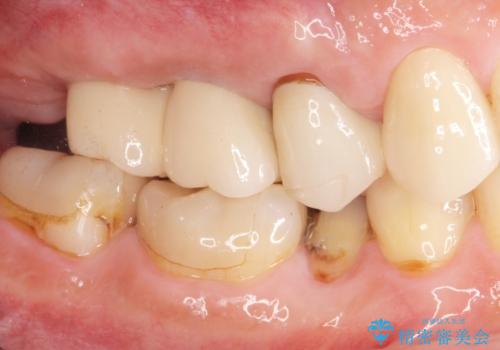

人工歯根であるインプラントを埋入することで奥歯でまたしっかりと噛める咬合機能を回復します。

- 88万円(インプラント×2・仮歯×2・チタンカスタムアバットメント×2・ジルコニアクラウン×2)費用は治療当時の料金となります

またしっかりと噛めるようになり、食事を楽しめるようになった!と喜んでいただくことができました。